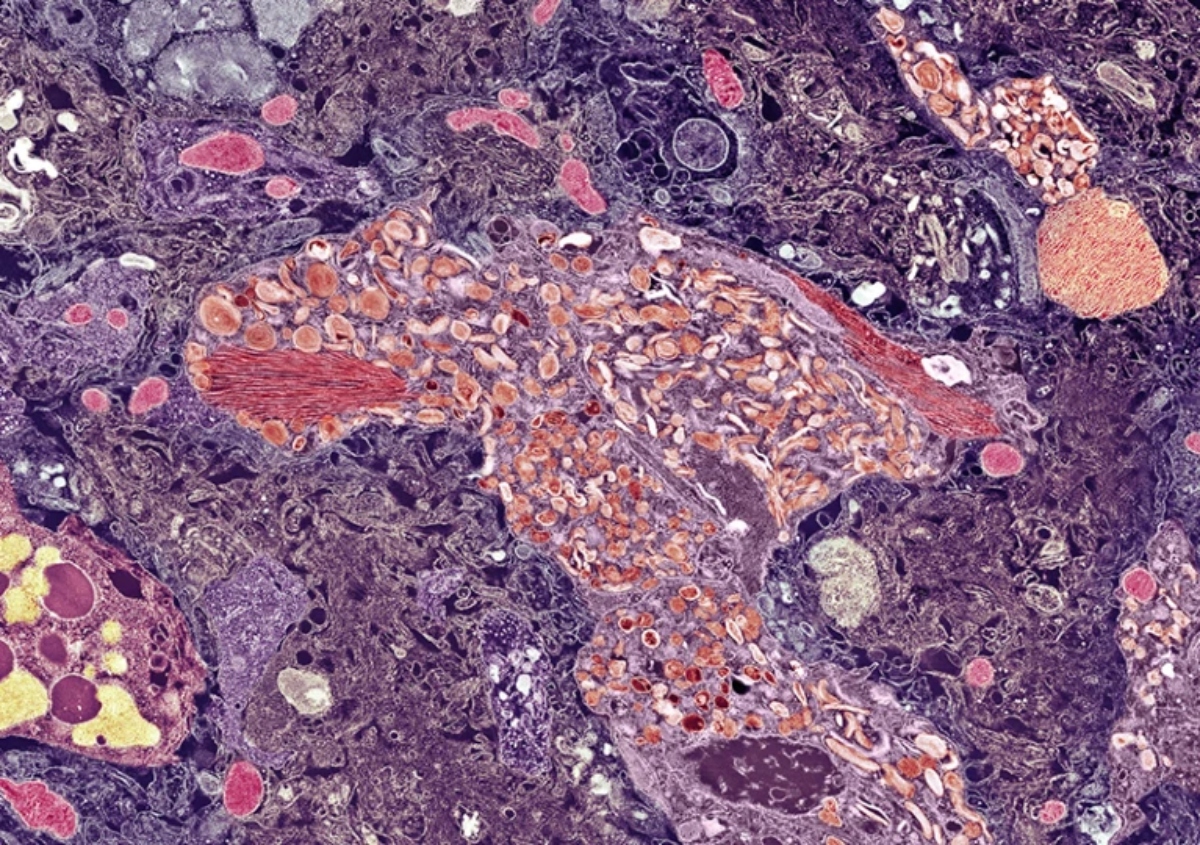

Ο Κολομβιανός άνδρας που εντοπίστηκε πρόσφατα συνέχισε να εργάζεται μέχρι να συνταξιοδοτηθεί στα 60 του και στα 67 του εμφάνισε τα πρώτα σημάδια γνωστικής έκπτωσης. Οι σαρώσεις αποκάλυψαν ότι ο εγκέφαλός του είχε ατροφήσει και εμφάνιζε τα κλασικά, μοριακά χαρακτηριστικά της νόσου: μεγάλο αριθμό κολλώδων πρωτεϊνικών συσσωματωμάτων και πρωτεϊνών tau. Αυτού του είδους τα συσσωματώματα παρατηρούνται συνήθως σε άτομα με σοβαρή άνοια.

Σε ένα μικρό, συγκεκριμένο τμήμα του εγκεφάλου του, όπου οι νευρώνες εμπλέκονται στη μνήμη και την πλοήγηση, ο άντρας είχε πολύ χαμηλά επίπεδα πρωτεΐνης tau. Η προστατευτική πρωτεΐνη κρατούσε τη νόσο Αλτσχάιμερ μακριά σε αυτή την κρίσιμη περιοχή του εγκεφάλου που συνήθως υποκύπτει στη νόσο αρκετά νωρίς.